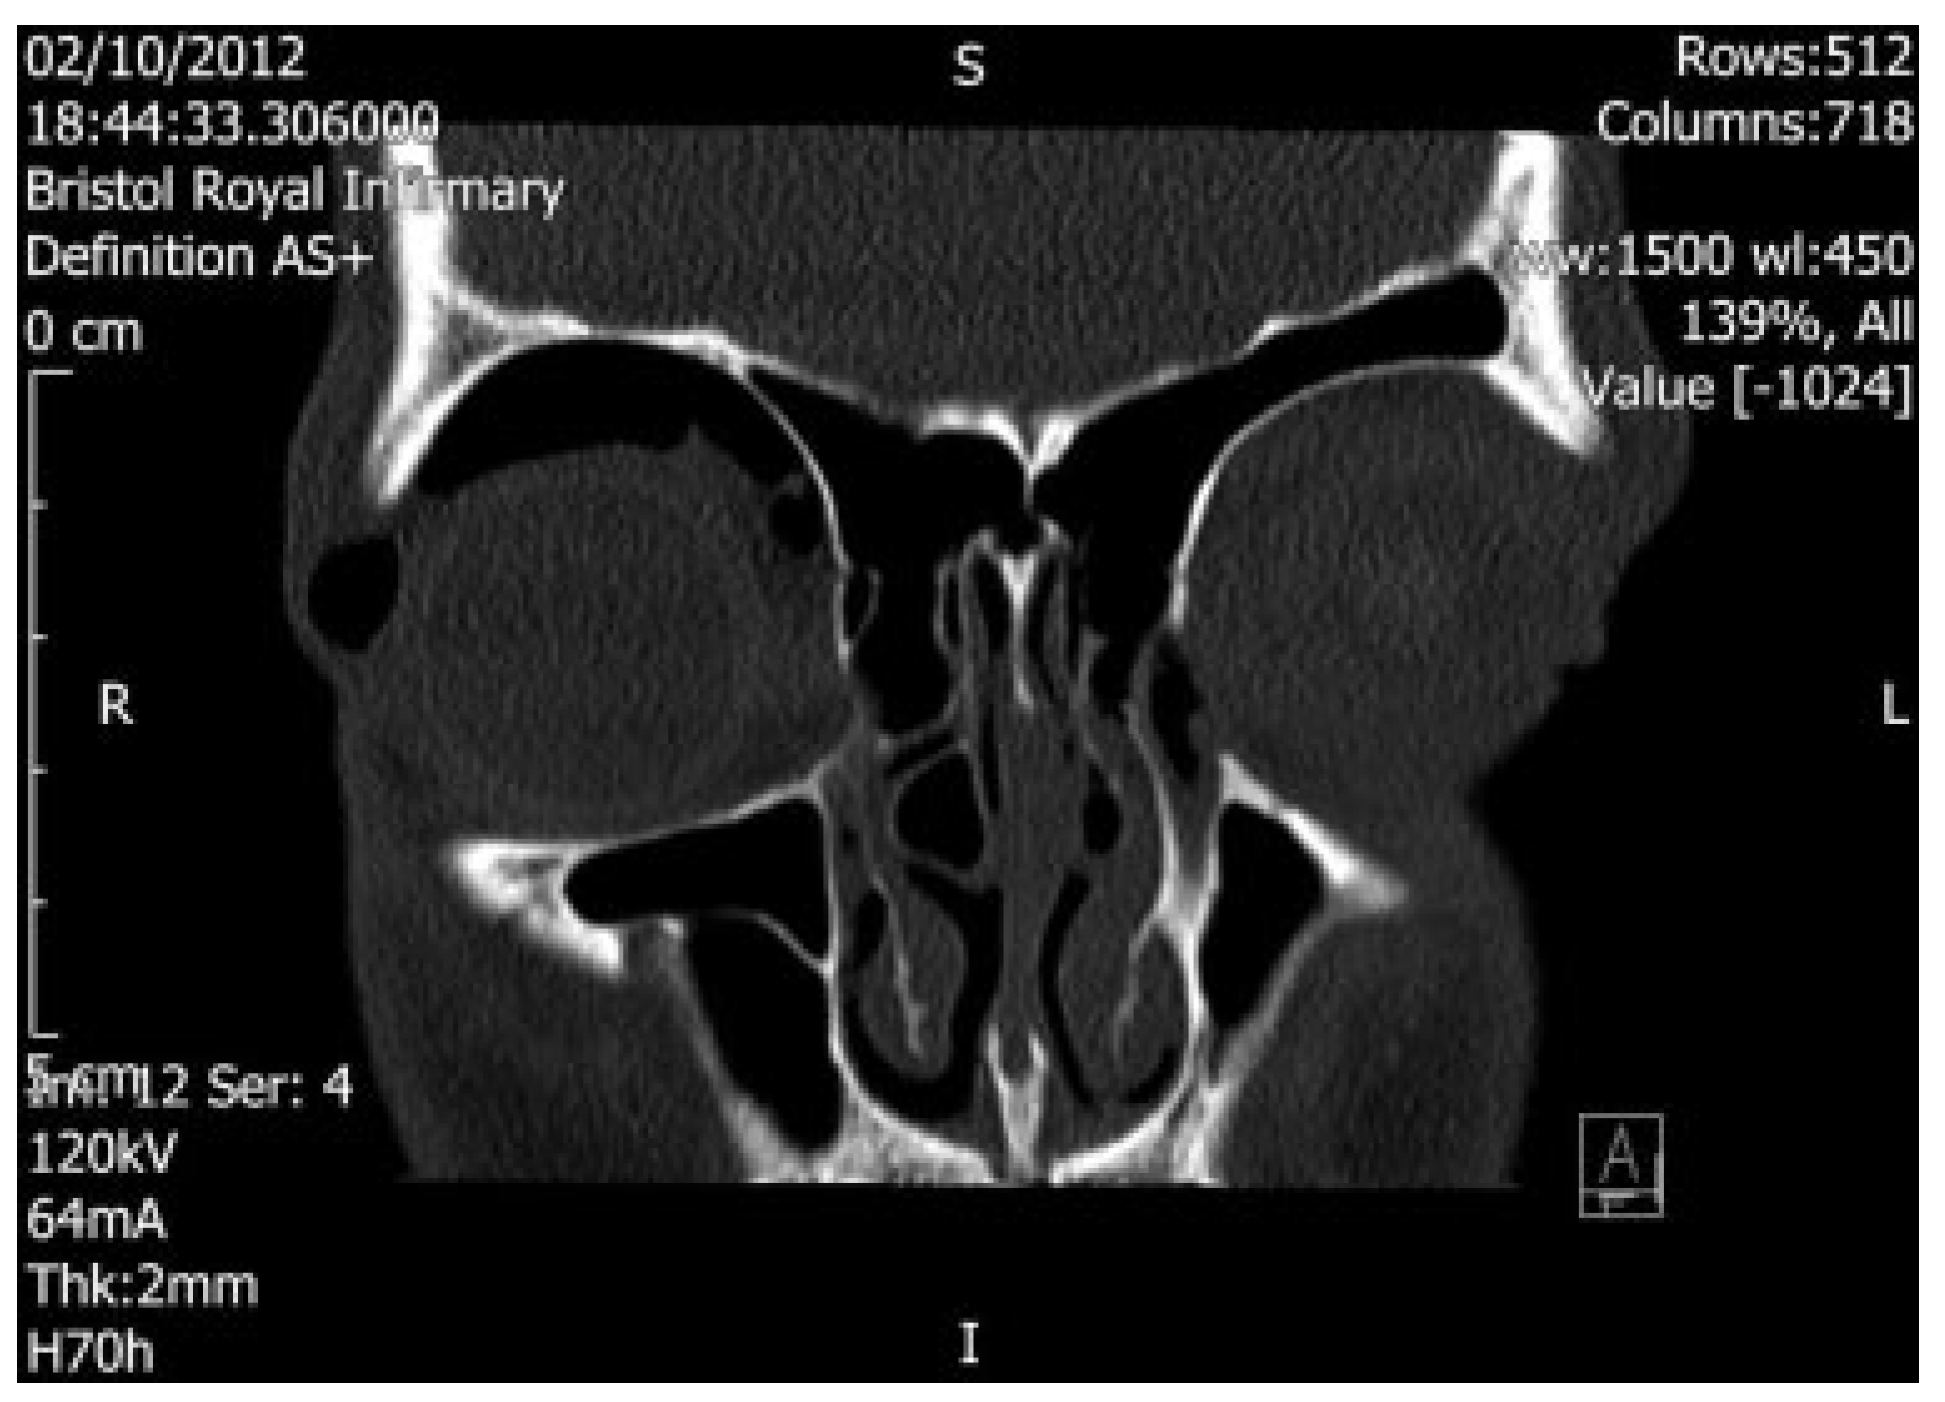

Medial Wall Fracture and Orbital Emphysema Mimicking Inferior Rectus Entrapment in a Child

:Case Report